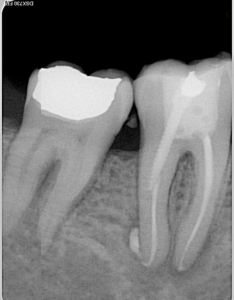

Le patient âgé de 45 ans consulte avec une fistule en vestibulaire de la dent 47. Il est en bonne santé générale et ne présente pas de douleur particulière.

La 46 a été traitée par un confère trois mois environ avant cette consultation.

La 47 est légèrement mobile et ne répond pas aux tests de sensibilité.

A l’examen clinique, sans Microscope opératoire, on note la présence d’une fissure occluso-distale qui ne semble pas s’étendre au-delà de la partie coronaire. Le sondage parodontal est de 2mm tout autour de la dent.

Le diagnostic de nécrose pulpaire étant posé de façon assez évidente sur la 47, le traitement canalaire a été réalisé en première intention. Le traitement a été fait en une seule séance avec une obturation canalaire avec une technique de gutta chaude. Une restauration coronaire foulée a été faite dans les jours suivants.

Sur la 46, une préparation périphérique a été faite et une couronne provisoire mise en place. Après réflexion, le retraitement canalaire de la dent n’a pas été reconsidéré, malgré la détection d’un élargissement apical sur la racine mésiale. La décision de non ré-intervention a été basée sur le fait que le traitement a été fait récemment et il est décidé de suivre son évolution et son efficacité malgré le fait que techniquement, il aurait pu être amélioré.